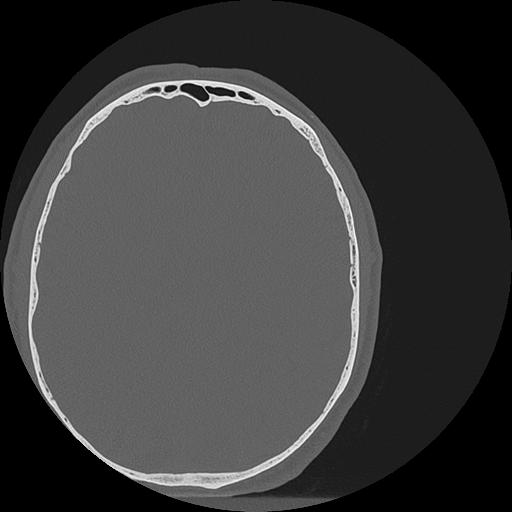

7 HUESO,,Vol,0.5,HUESO,,